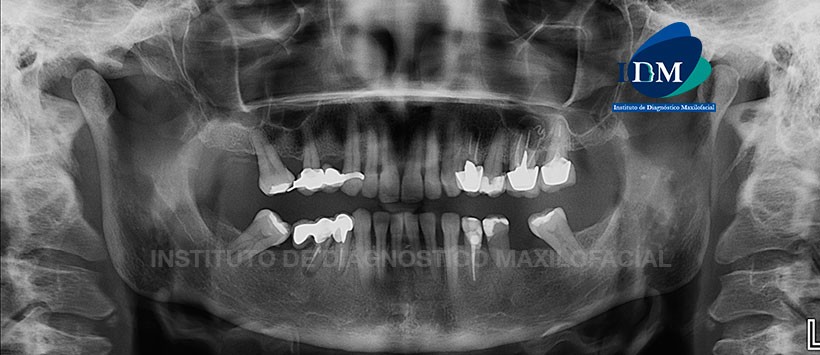

Paciente masculino de 56 años de edad acude al Instituto de Diagnóstico Maxilofacial por molestia en zona molar de lado izquierdo.

A la evaluación panorámica se aprecia neumatizacion alveolar de ambos senos maxilares, leve reabsorción osea alveolar bimaxilar, edentulo parcial bimaxilar, y múltiples restauraciones. En la evaluación de las piezas dentarias apreciamos que existen múltiples piezas con material de obturación de conducto, espigos y corona protésicas; siendo la mas resaltante la pieza 26. Esta pieza presenta una corona protésica con aparente falta de sellado en zonas proximales, espigo y material de obturación de conducto con una aparente sobreobturacion; así mismo se aprecia un proceso osteolitico a nivel apical de forma redondeada con limites definidos y bordes corticalizados. (Figura 1)